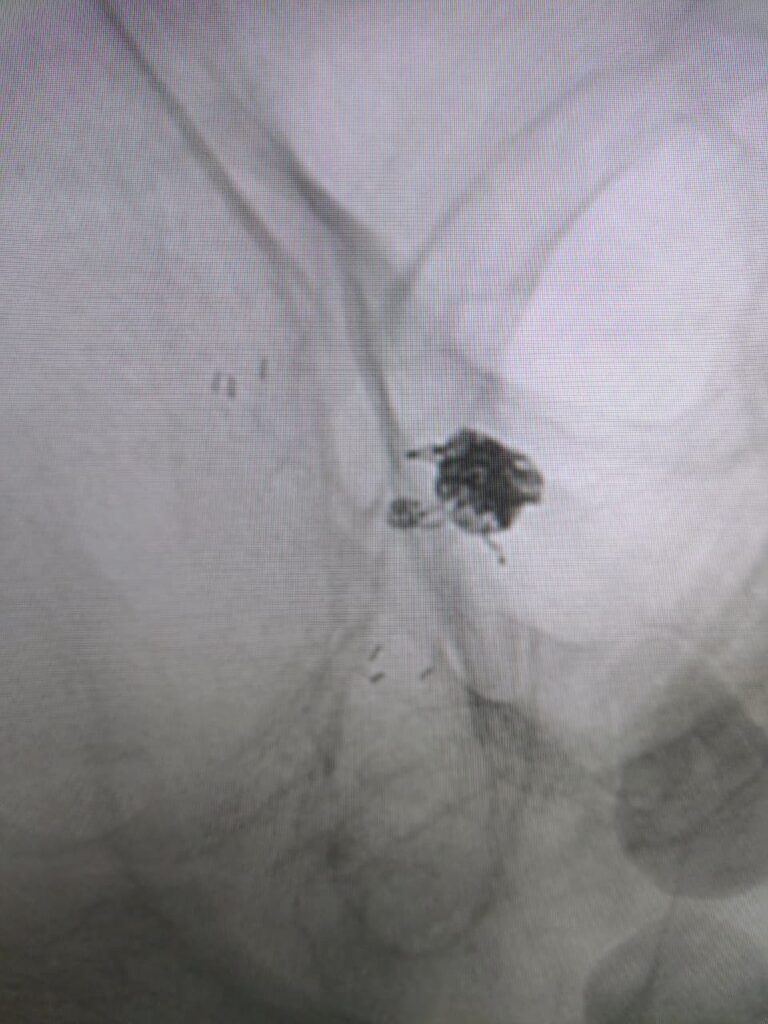

Ruptured Brain aneurysm (left ICA communicating segment wideneck aneurysm) treated with Stent Assisted Coiling.

aneurysm cannulated with microcatheter and microwire